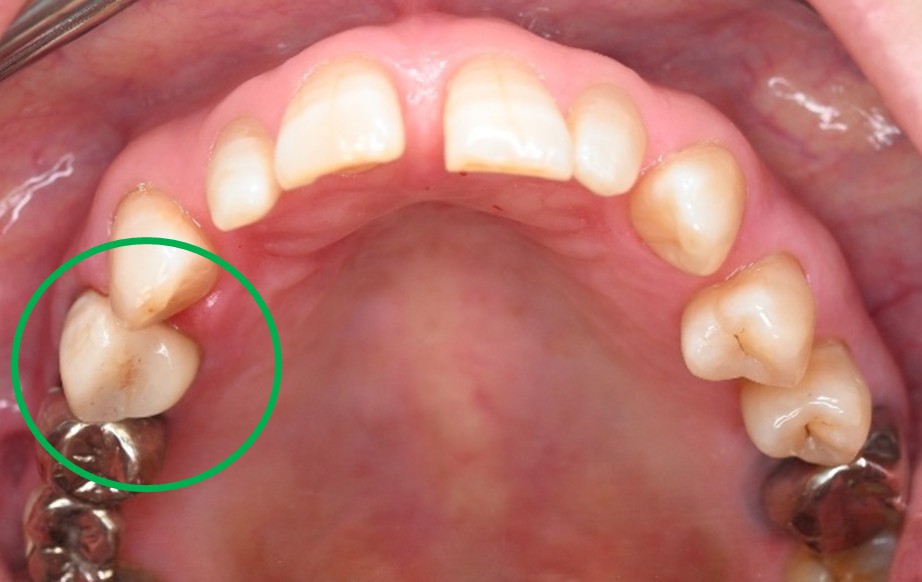

男性 Mさん 50代 (オールセラミック冠)

主訴

右上奥歯が、冷たいものにしみる。

治療内容

歯髄(神経および血管)まで到達する大きな虫歯でしたので、抜髄(歯髄を取り除く)をし、ファイバーコアをいれ、オールセラミック冠を被せました。

所感

現在、保険治療において、限定的ではありますが、大臼歯にも白い被せ物(プラスチック冠)ができるようになりました。しかし、実感としてプラスチック冠は、

- すり減りやすい。割れることがある。

- バイオフィルム(細菌およびそれから産生される副産物の塊)が付着しやすいので、歯周病および2次カリエス(被せ物と自分の歯の境目から再度虫歯になる)になるリスクが高い。

- 変色する。

という点を感じます。白い被せ物が保険の治療でできるという理由で、安易にプラスチック冠を選択し、割れたりすり減ったり、変色したらもう一度被せなおせばいいと考えるのであれば、一度立ち止まって考えてみてください。歯の量は、治療するたびに薄く少なくなり、歯根破折のリスクが高まります。もし大きな虫歯になってしまったら、最高レベルの根管治療をし、最良の被せ物であるオールセラミック冠を被せ、定期的にお口の中のクリーニングをし、同じ歯を2度と治療しないことが、歯を長持ちさせる最良の方法だと考えます。

オールセラミック冠(失活歯):¥104,500(税込)

Before

劣化したプラスチック冠

After